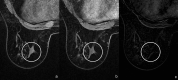

Radial scar (RS) or complex sclerosing lesions (CSL) if > 10 mm is a benign lesion with an increasing incidence of diagnosis (ranging from 0.6 to 3.7%) and represents a challenge both for radiologists and for pathologists. The digital mammography and digital breast tomosynthesis appearances of RS are well documented, according to the literature. On ultrasound, variable aspects can be detected. Magnetic resonance imaging contribution to differential diagnosis with carcinoma is growing. As for the management, a vacuum-assisted biopsy (VAB) with large core is recommended after a percutaneous diagnosis of RS due to potential sampling error. According to the recent International Consensus Conference, a RS/CSL lesion, which is visible on imaging, should undergo therapeutic excision with VAB. Thereafter, surveillance is justified. The aim of this review is to provide a practical guide for the recognition of RS on imaging, illustrating radiological findings according to the most recent literature, and to delineate the management strategies that follow.